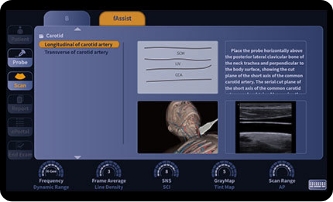

fAssist

Oferowanie informacji tutorialowych dotyczących jamy brzusznej, naczyń krwionośnych, małych części, GYN (ginekologia i położnictwo), MSK (układ mięśniowo-szkieletowy) itp., zawierających standardowe obrazy ultrasonograficzne, diagramy anatomiczne, techniki skanowania oraz wskazówki.